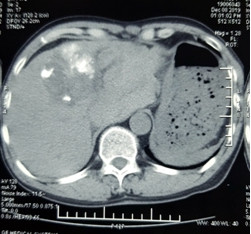

Các bác sĩ Bệnh viện Ung Bướu Hà Nội vừa thực hiện thành công ca cấp cứu u gan vỡ gây mất máu cấp, có nguy cơ tử vong cao nếu không được can thiệp kịp thời. Bệnh nhân được cầm máu bằng phương pháp nút tắc động mạch gan, giúp vượt qua “cửa tử”. Bệnh nhân Ngô Văn S., 59 tuổi, trú tại Hoàng Mai – Hà Nội mắc ung thư gan, khối u có đường kính 6 cm, lồi khỏi mặt dưới gan trái, đã được nút mạch hóa chất cách đây 3 tháng, sức khỏe ổn định. Đến sáng chủ nhật ngày 8/12/2019, bệnh nhân được người nhà đưa đến Bệnh viện Ung Bướu Hà Nội trong tình trạng đau bụng dữ dội vùng thượng vị, hoa mắt chóng mặt, da nhợt nhạt, mạch nhanh 140 lần/phút, huyết áp tụt còn 90/70 mmHg. Qua siêu âm, các bác sĩ phát hiện có nhiều máu trong ổ bụng bệnh nhân. Kết quả chụp cắt lớp vi tính cho thấy, khối u gan kích thước hơn 6 cm thâm nhiễm nhu mô gan trái đã vỡ, còn đang có dấu hiệu chảy máu, tạo khối máu tụ lớn khoang hậu cung mạc nối, nhiều dịch máu quanh gan và tiểu khung, chỗ dày nhất 6 cm. Bệnh nhân được chẩn đoán sốc mất máu do u gan vỡ, nguy cơ tử vong cao. Trước tình huống nguy kịch của bệnh nhân, BSCKII. Nguyễn Đình Hướng – Trưởng Khoa Chẩn đoán hình ảnh đã hội chẩn cấp cứu và quyết định thực hiện kỹ thuật nút tắc động mạch gan để cầm máu u gan vỡ trên hệ thống máy chụp mạch số hóa xóa nền (DSA). Các bác sĩ khoa Chẩn đoán hình ảnh, Phẫu thuật – Gây mê Hồi sức đã khẩn trương sắp xếp hệ thống và tiến hành thủ thuật nhanh nhất có thể để “chạy đua” với “tử thần”. Cụ ông vỡ u gan, máu tràn ngập ổ bụng mà không hề biết ảnh 1Hình ảnh khối u gan hạ phân thùy IV bị vỡ gây khối máu tụ lớn quanh gan trái Bác sĩ Hướng cho biết: “Nếu không được xử trí ngay, bệnh nhân sẽ bị mất máu ồ ạt trong ổ bụng dẫn đến tử vong chỉ trong thời gian ngắn. Nút mạch gan là chỉ định hàng đầu để xử trí trong trường hợp này nhằm cứu sống bệnh nhân. Kỹ thuật can thiệp nút mạch sẽ bít tắc được mạch máu bị vỡ (nguyên nhân chảy máu), giúp bệnh nhân cầm máu tức thì, tránh nguy cơ tử vong. Hơn nữa, vị trí luồn thiết bị can thiệp kích thước nhỏ như vết tiêm truyền mạch máu, ít gây đau đớn, không để lại sẹo và thời gian hồi phục sức khỏe sau thủ thuật của bệnh nhân nhanh, ít tai biến so với các phương pháp điều trị khác.” Cụ ông vỡ u gan, máu tràn ngập ổ bụng mà không hề biết ảnh 2Hình ảnh động mạch thân tạng chụp bằng máy chụp mạch số hóa xóa nền: động mạch gan trái và phải còn đang có dấu hiệu chảy máu ra ngoài gan. Ca phẫu thuật diễn ra trong khoảng 30 phút. Sau khi nút tắc động mạch mạch gan, huyết động của bệnh nhân ổn định ngay. Huyết áp tăng lên 110/70 mmHg, mạch đo được 100 lần/phút. Theo dõi sau 1 tuần, mạch và huyết áp đều ổn định, chụp cắt lớp vi tính kiểm tra lại thấy động mạch gan trái và phải tắc hoàn toàn, khối u không còn tăng sinh mạch, không còn dấu hiệu chảy máu ra ngoài khối u, lượng máu tụ trong ổ bụng đã giảm 50%. Trải qua cơn “thập tử nhất sinh”, ông Ngô Văn S. chia sẻ: “Lúc vào viện tôi đau bụng quằn quại, cứ nghĩ mình sắp chết đến nơi. Rất may, tôi đã được các bác sĩ đưa đi cấp cứu rất nhanh, kịp thời cứu sống. Giờ sức khỏe tôi đã ổn hơn nhiều, ăn uống tốt rồi.” Cụ ông vỡ u gan, máu tràn ngập ổ bụng mà không hề biết ảnh 3Bệnh nhân S. tươi tỉnh sau 1 tuần được phẫu thuật cấp cứu Chụp và nút động mạch dưới máy chụp mạch số hóa xóa nền là kỹ thuật hiện đại trong điều trị bệnh lý khối u khi không có chỉ định can thiệp bằng phẫu thuật hoặc tiến hành trước phẫu thuật để tạo thuận lợi tránh các biến chứng chảy máu trong cuộc mổ cho bệnh nhân, mang lại nhiều cơ hội cứu sống người bệnh ung thư, nhất là ung thư gan. Đây là kỹ thuật nút mạch cấp cứu tương đối phức tạp, đòi hỏi bác sĩ điện quang can thiệp phải có kinh nghiệm và kĩ năng chuyên sâu, bài bản, trang thiết bị - vật tư y tế hiện đại đầy đủ và đồng bộ sẽ giúp bệnh nhân tránh được ca đại phẫu với thời gian nằm viện điều trị dài ngày, nguy cơ tử vong do mất máu và các biến chứng hậu phẫu. Kỹ thuật này ưu việt hơn rất nhiều so với trước đây, để điều trị u gan vỡ chảy máu cấp ổ bụng, bệnh nhân phải trải qua cuộc đại phẫu nặng nề, mất máu, vết mổ hở gây đau đớn, thời gian nằm viện kéo dài, tai biến trong cuộc mổ cũng như hậu phẫu phức tạp, hay gặp hơn. Kỹ thuật điện quang can thiệp đã được thực hiện thường quy từ nhiều năm nay tại Bệnh viện Ung Bướu Hà Nội, áp dụng cho rất nhiều các bệnh lý của các cơ quan bộ phận khác nhau như: u gan, u xơ tử cung, các u máu hàm mặt, các u máu phần mềm, các can thiệp tiết niệu và đường mật .... và rất nhiều các bệnh lý khác giúp bệnh nhân tránh được các cuộc đại phẫu nguy hiểm, nâng cao tỉ lệ cứu sống người bệnh, giảm chi phí và thời gian nằm viện. Quảng An #u gan #nút tắc động mạch gan